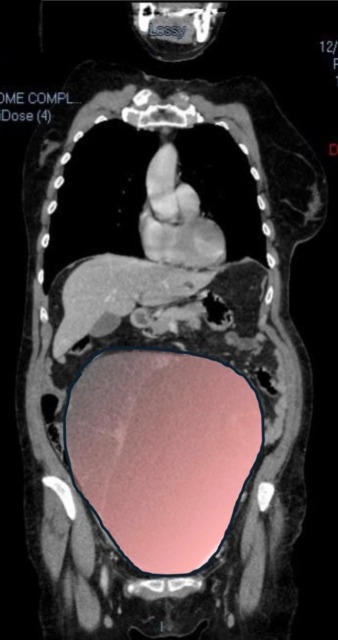

La gigantesca cisti ovarica, con un diametro di circa 28 centimetri, è rimasta nascosta per mesi senza dare segnali evidenti. L’allarme è scattato improvvisamente quando la massa, associata a una seconda neoplasia intestinale, ha iniziato a comprimere il colon, provocando una grave sofferenza intestinale non più ignorabile.

Fondamentale il contributo della Radiologia del Sant’Anna, che fornisce l’imaging preoperatorio indispensabile per affrontare un quadro clinico di estrema complessità.